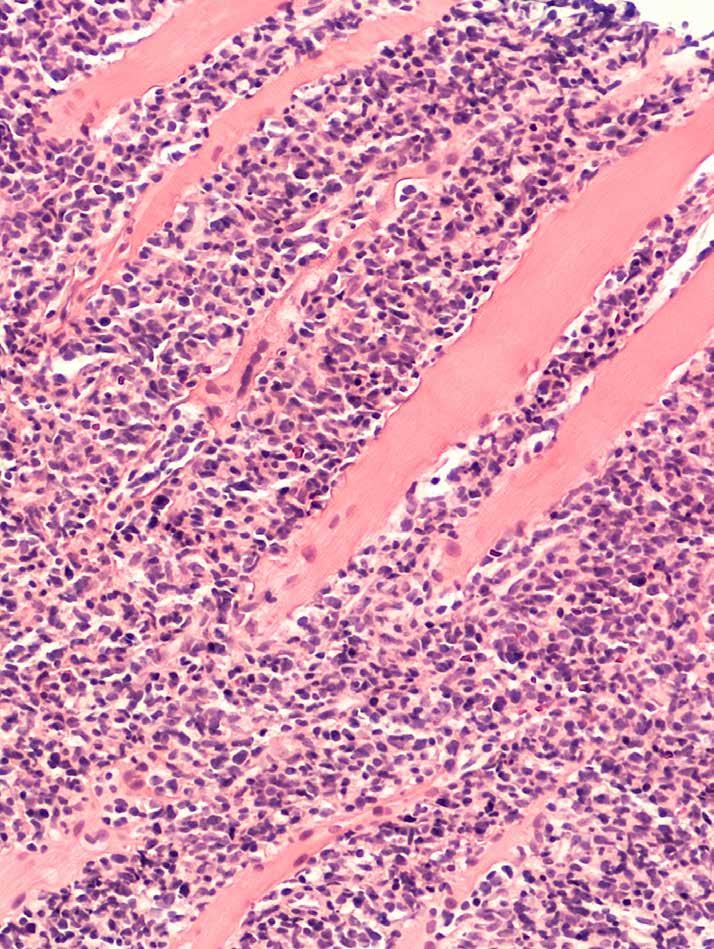

De diagnose wordt gesteld op basis van een biopsie, waarbij een opgezette lymfeklier of een stuk weefsel uit het verdachte orgaan wordt verwijderd. De cellen in die klier worden daarna onder een microscoop onderzocht door een patholoog. Daarnaast zullen testen worden gedaan om bepaalde eiwitten op te sporen, en eventuele veranderingen in het genetisch materiaal (DNA) van de cellen. Dit microscopisch onderzoek (histologie of histopathologie genoemd) wordt gebruikt om de diagnose te stellen, maar ook om het type lymfoom te bepalen. Het is belangrijk om het type lymfoom te kennen om te beslissen over de behandeling en een idee te hebben over de prognose.

In 95% van de hodgkingevallen gaat het om klassiek hodgkinlymfoom2, een categorie waarin de patholoog door weefstelstalen nog vier subtypes kan onderscheiden gebaseerd op hoe ze eruit zien onder de microscoop:

Deze subtypes worden gedefinieerd op basis van hun uitzicht onder de microscoop (morfologie), hun interne en externe kenmerken (immunofenotypering), en hun genetische kenmerken. Bepaalde subtypes vereisen een specifieke behandeling, dus het is van groot belang het juiste subtype te diagnosticeren.